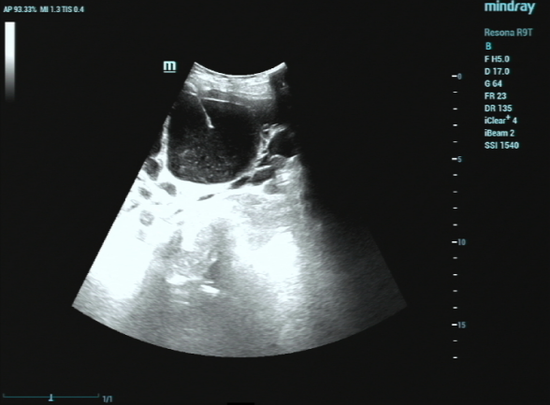

1. 精准定位: 超声就像医生的“透视眼”。在治疗前,超声仪器会清晰地显示囊肿的大小、位置,以及与周围大血管、脏器的关系,规划出最安全的进针路线。

2. 细针穿刺: 局部麻醉后,医生用一根很细的穿刺针(比平时打针的针头粗不了多少),在超声的实时监控下,精准地刺入囊肿中心。

3. 抽液硬化:先将囊内的液体抽干净,然后注入硬化剂(通常是无水酒精或聚桂醇)。这个硬化剂的作用是破坏分泌囊液的“囊壁细胞”,让它失去分泌功能,就像把水泡的内壁“烫”一下,让它粘合在一起。

整个治疗在超声设备的实时引导下进行,医生可以清晰看到穿刺针的路径,避开重要的血管和神经,从而在精准治疗的同时,进一步降低并发症风险。